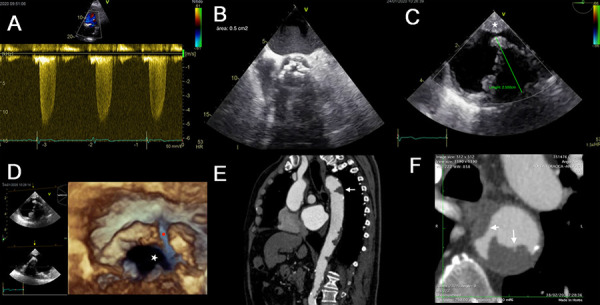

Aortic stenosis is associated with aortic plaques in up to 85% of cases because they share risk factors and pathogenic pathways. Intrinsically, complex aortic plaques carry a high risk of stroke, which has also been demonstrated in the context of aortic stenosis, especially in patients who underwent percutaneous or surgical replacement. Transesophageal echocardiography (TEE) is the imaging test of choice to detect plaques in the thoracic aorta and classify them as complex plaques. Furthermore, the 3D modality allows us to better specify its dimensions and anatomical characteristics, such as added thrombi or the presence of ulcers inside. This review aims to evaluate the use of TEE to detect complex aortic plaques in patients with an indication for percutaneous or surgical aortic valve replacement. To highlight the association between aortic stenosis and complex aortic plaques, we attached to the review some TEE studies from our experience.